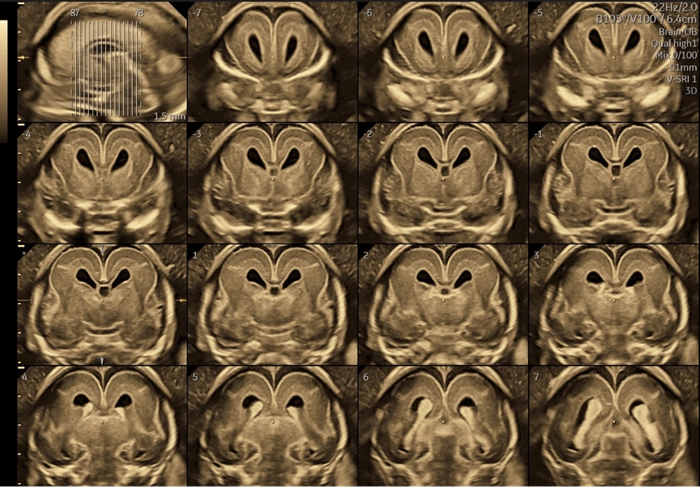

対象:1,000人以上の胎児

方法:高精度3D経膣脳神経超音波による脳の詳細計測

結果:先天異常を持つ胎児群を複数のグループに分類し、サブプレートの発達パターンを比較分析した結果、グループ間で明確な発達の違いを確認。